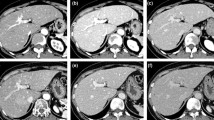

Saline solution flush following contrast material bolus led to statistically significantly higher parenchymal and vascular enhancement. The mean parenchymal enhancement was 8±12 HU higher with double-syringe power-injector protocol. Table 2 shows the attenuations values of both protocols and the differences in attenuation between both protocols for the parenchymal organs and the vessels. Figure 1 shows the relation of mean parenchymal and vascular attenuation between both protocols.

Relation of mean parenchymal and vascular enhancement (mean±SD) after contrast material administration for single-syringe power injector (triangles) and double-syringe power injector (squares). Double-syringe power-injector protocol produced statistically significantly higher enhancement values than single power-injection protocol (p<0.05)

There was no significant difference in mean enhancement along the z-axis for the parenchymal organs for both protocols. With the single-syringe power-injector protocol, the mean enhancement of the superior liver segments was 106±12 HU, of the inferior liver segments 105±11 HU (p=0.123). The corresponding enhancement values were 105±12 and 106±12 HU for the superior and inferior pole of the spleen (p=0.199) and 150±27 and 151±26 HU for the superior and inferior pole of the kidneys (p=0.451). With the double-syringe power-injector protocol, the corresponding enhancement values were 114±15 and 113±13 HU for the liver (p=0.128), 112±13 and 114±15 HU for the spleen (0.120), and 159±26 and 160±31 HU for the kidneys (p=0.316; Fig. 2).

Mean enhancement (mean±SD) of the superior pole (s) and inferior pole (i) of the liver, spleen and renal cortex for single-syringe power injector (triangles) and double-syringe power injector (squares). Note that there is no statistically significant difference in mean enhancement between superior and inferior pole of the organs (p<0.05)

All examinations were performed on the same MDCT scanner with the same scanning parameters, as using different CT scanners may result in measurement errors as reported by Levi et al. [21]. They reported significant differences in absolute Hounsfield units between most scanners even two scanners of the same manufacturer and model. We consider that as an important advantage of our study compared with other studies, where parenchymal enhancement was measured to evaluate different contrast material doses or injection rates using data of different patients and different CT scanners. The improvement of temporal resolution of MDCT enables scanning the abdomen during the peak plateau of contrast material enhancement. Consequently, we achieved a uniform contrast material enhancement of all parenchymal organs regardless of the position along the z-axis. There was no statistically significant difference in mean parenchymal enhancement of all liver segments and between the superior pole and the inferior pole of the spleen and the kidneys, respectively (Fig. 2).